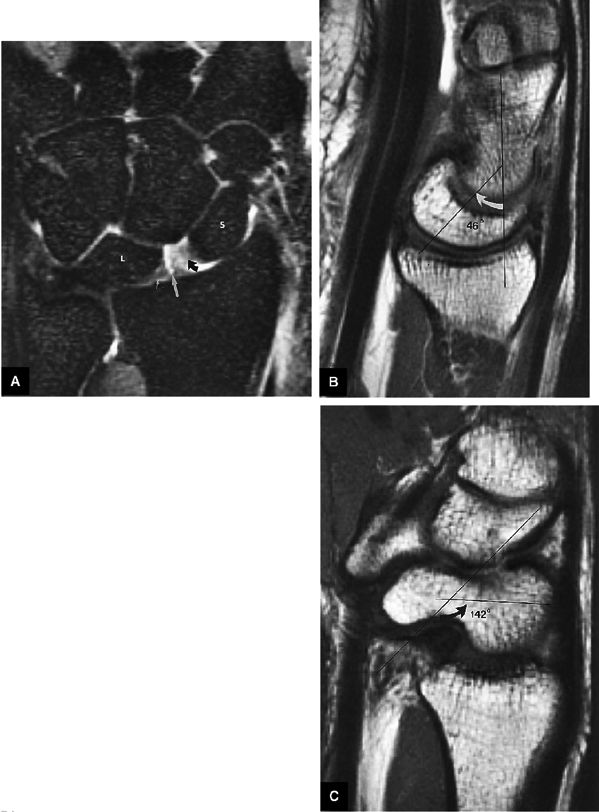

|

FIGURE 10.90 ● Scapholunate ligament tear with DISI. (A) Traumatic avulsion of the lunate aspect of the scapholunate ligament on a fast STIR coronal image. The scapholunate interval is widened with direct extension of fluid filling the tear site (large straight arrow). Ligament fibers are still attached to the radial aspect of the lunate (small straight arrow). Morphology is amorphous at the avulsed scaphoid remnant (curved arrow). (B) The capitolunate angle (arrow) is increased to 46°, and there is associated dorsal tilting of the lunate. (C) The scaphoid tilts palmarly with an increased scapholunate angle (arrow) of 142°.